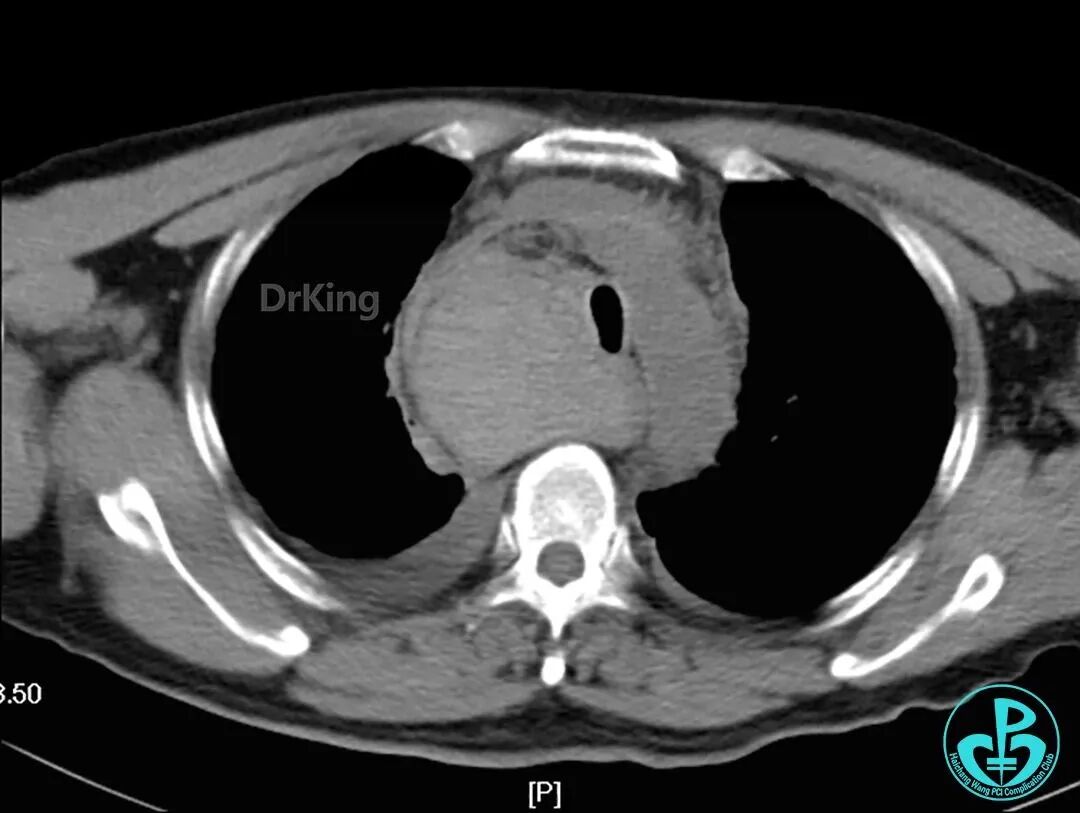

主动脉弓层面前后CT对照。

泥鳅导丝怎么用超滑泥鳅导丝致纵隔血肿,保守治疗血肿吸收_https://www.jmylbn.com_新闻资讯_第14张